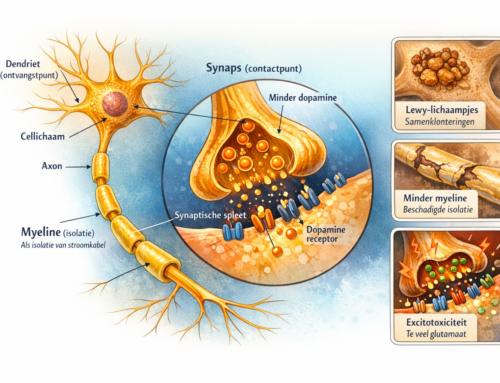

Wanneer je lichaam teveel stress heeft dan is het hormoon adrenaline al snel verhoogd. Hierdoor kun je vaak doorgaan en doorgaan zonder te voelen hoe moe je eigenlijk bent. Ook allergieën en zware diëten kunnen dit hormoon activeren.

Wanneer je een hele ernstige vorm van bijnieruitputting hebt zal het door de reguliere gezondheidszorg ontdekt worden en behandeld (let op deze doen verder niks met voeding terwijl dit wel een meespelende factor is), maar een milde vorm ontdekken ze niet snel en dus loop je soms wel jaren rond met vage klachten zoals: constant moe voelen, allergisch zijn/ worden, artritis, verminderd immuniteitssysteem, suikerspiegelschommelingen, spijsverteringsproblemen enz. Door die suikerspiegel- schommelingen ga je automatische meer snelle en ongezonde koolhydraten eten of koffie drinken en hierdoor zullen de bijnieren nog verder overbelast worden en gaat je gezondheid verder achteruit.

Bij een FLINKE bijnieroverbelasting zie je ook vaak dat mensen weinig kunnen hebben en angstiger zijn. Ook kunnen ze zich verward of depressief voelen en komt slapeloosheid komt ook veel voor.